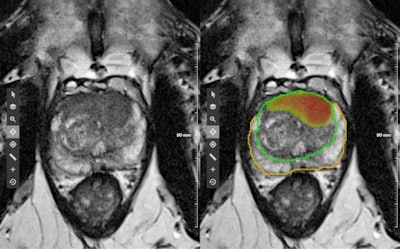

The study utilized a prototype of AI-CAD software (Prostate MR on syngo.via) from Siemens Healthineers. Two Siemens employees were also part of the research team.

The AI software led to better radiologist performance for detecting highly suspicious lesions.

"One of the main findings of our study was that the readers benefited statistically significantly from the software solution in terms of detection and classification when a threshold of PI-RADS ≥ 4, representing highly suspicious lesions, was applied," the authors wrote.